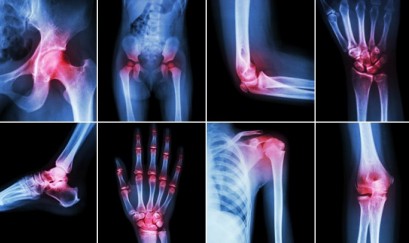

Dấu hiệu của bệnh viêm khớp

Viêm khớp là một một khái niệm chung để chỉ tình trạng viêm đau ở các khớp, bao gồm nhiều bệnh lí khớp nhau như gout, viêm khớp dạng thấp, viêm khớp ở trẻ em, bệnh lupus ban... [Đọc tiếp]

Viêm khớp dạng thấp là bệnh phổ biến trong xã hội, nếu không được phát hiện sớm và điều trị kịp thời sẽ gây ra những biến chứng nghiêm trọng làm hạn chế vận động và giảm chất... [Đọc tiếp]

Bệnh viêm đa khớp dạng thấp là một trong những nguyên nhân gây tàn tật hàng đầu trên thế giới. Theo các chuyên gia, những người bị viêm đa khớp dạng thấp 8 -10 năm, thì nguy cơ... [Đọc tiếp]